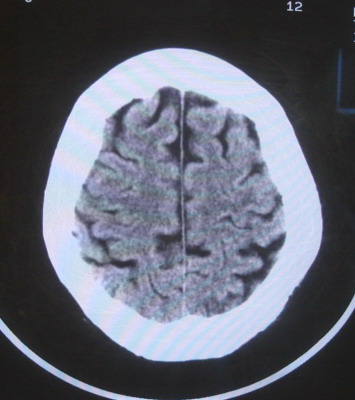

女  67岁 双下肢无力,行动不灵便

脑萎缩,腔隙性脑梗塞.

双侧额桥束及左侧脑室旁多发腔梗塞+老年性脑改变

多发腔梗、老年性脑改变、脑白质异常。